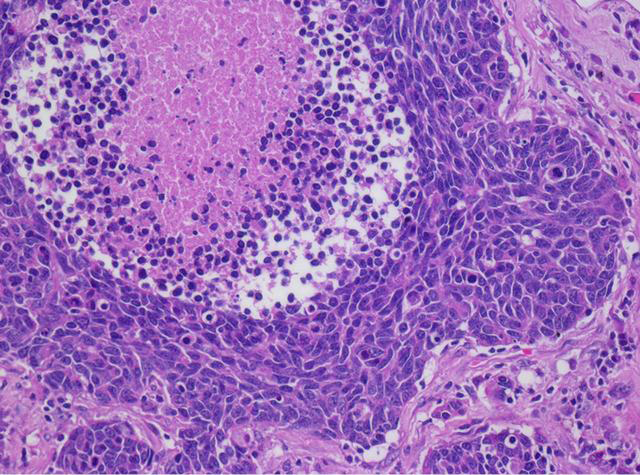

Click vào ảnh để xem 5 hình ảnh minh họa